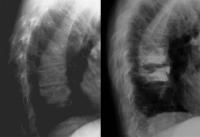

Vertebroplastie

Abbildung 7: Frische Frakturen des 9. und 10. BWK vor und nach Vertebroplastie (VAS prä 8, post 0).